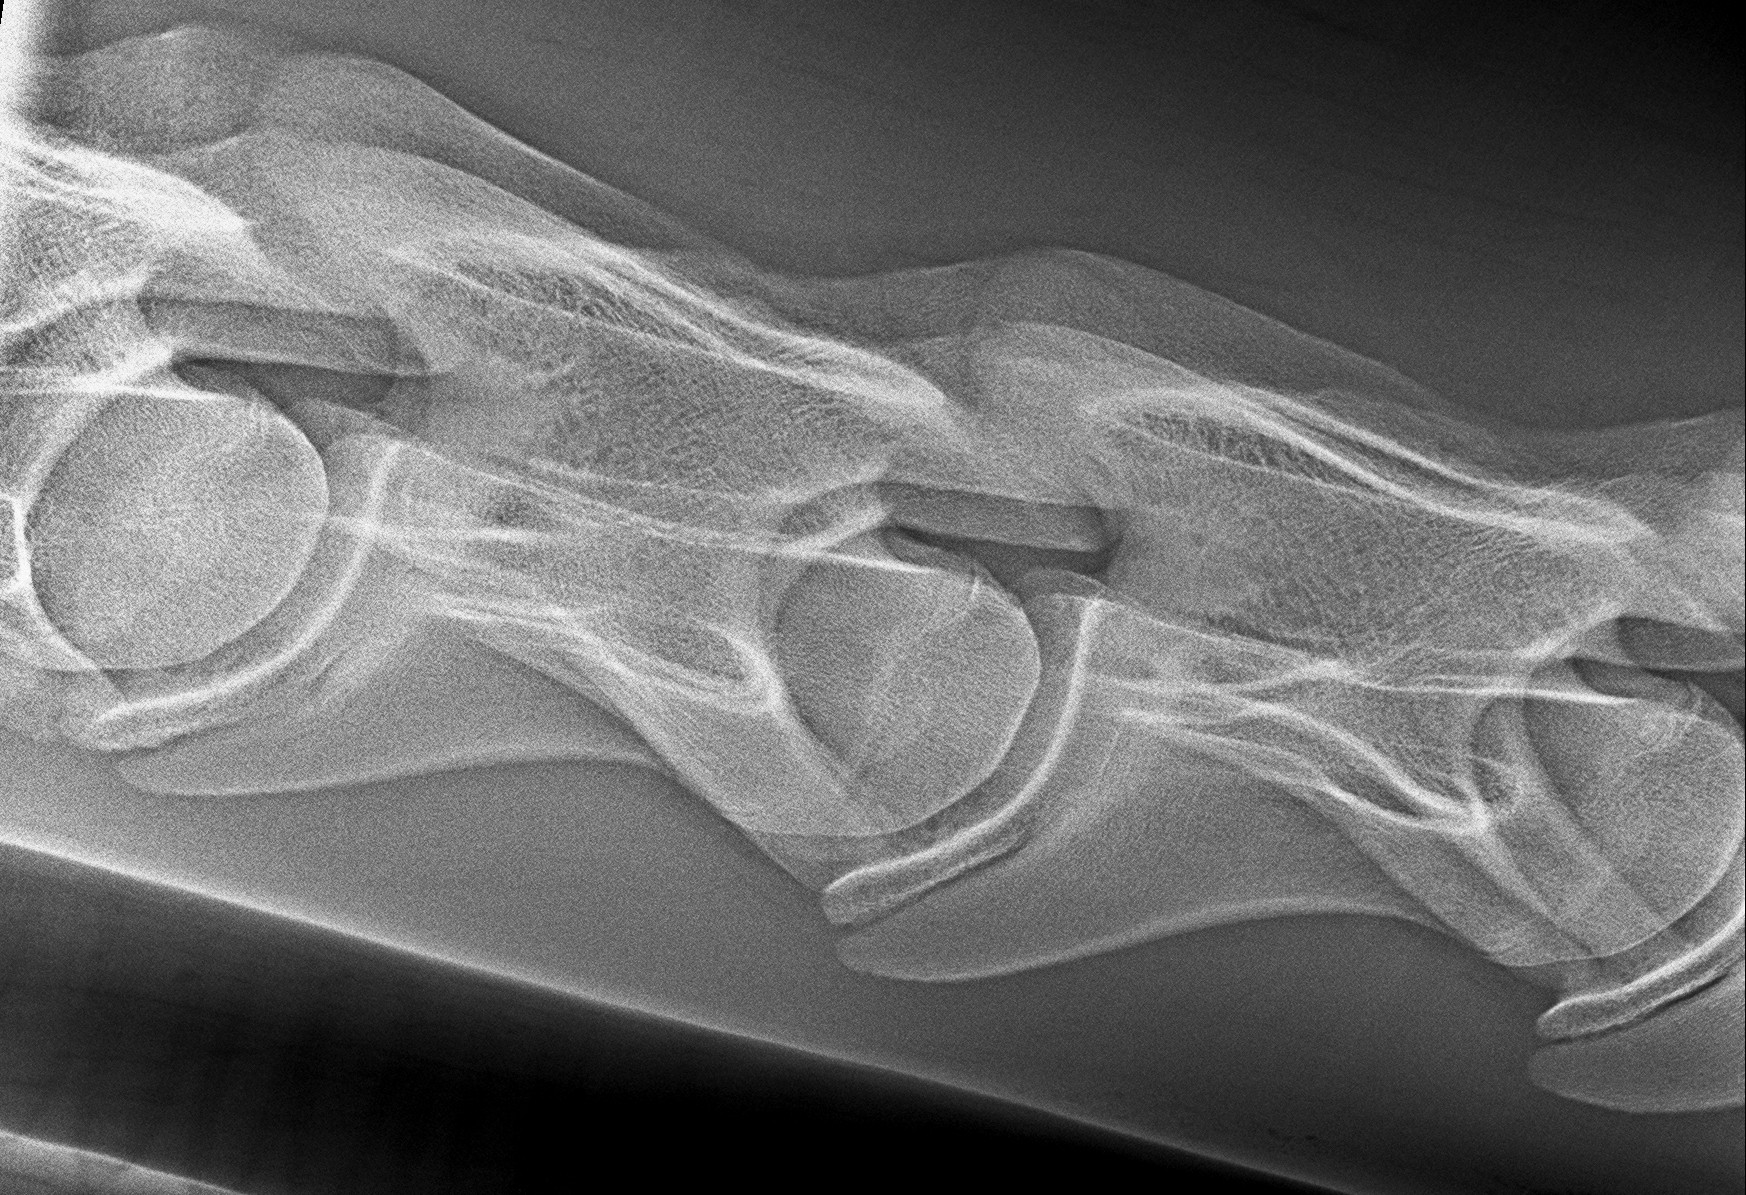

• Vizsgálat során a tünetek mellett Röntgen- és ultrahang vizsgálat jöhet szóba.